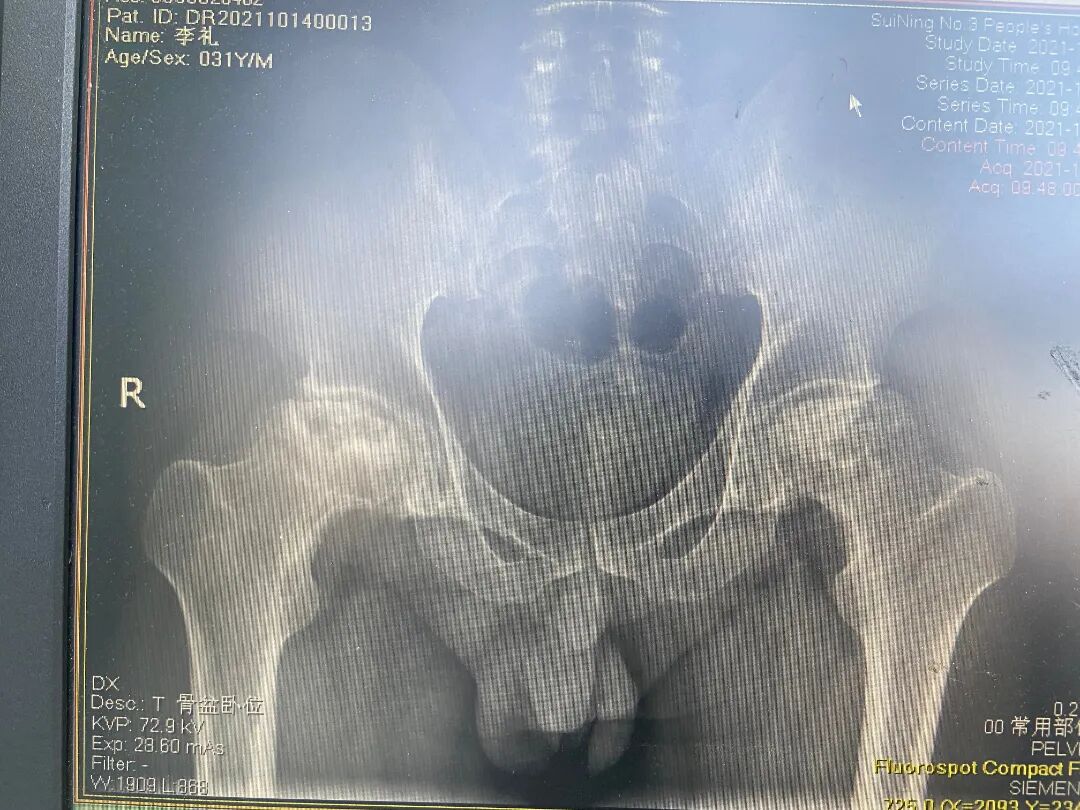

双侧股骨头坏死

双侧人工全髋关节置换术